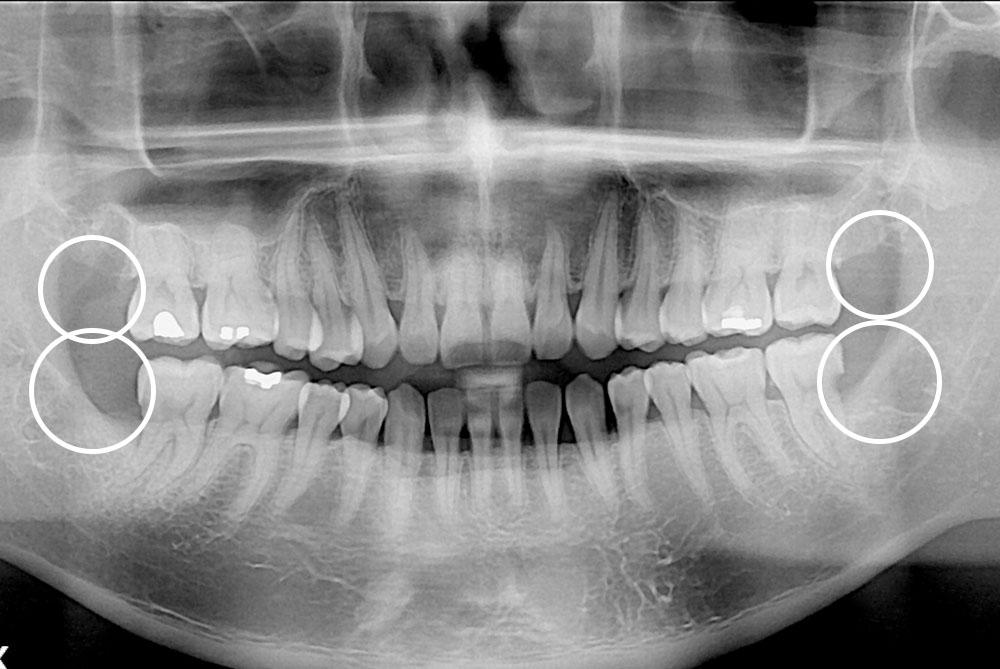

[사랑니] 매복 사랑니 발치

치료전 : 2018-02-23

치료후 : 2018-03-31

세종치과는 구강악안면외과학 박사이신 원장님이 발치하는 치과입니다.